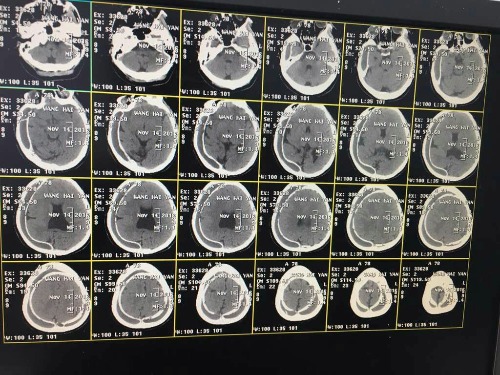

CT52392:头颅ct,比较罕见,分享下

本帖最后由 cefcmj 于 2016-11-22 20:34 编辑 就一张图片,转发的,比较罕见的病例

右侧额颞顶、左侧顶部颅板下可见线弧环状钙化影,透明隔缺如。两侧侧脑室融合畸形。考虑:骨膜下血肿骨化?硬膜下血肿骨化?

骨膜下血肿,脑发育不良